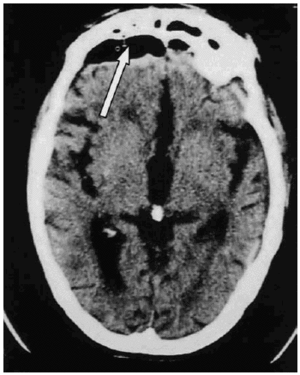

Se realizó una TAC craneal que demostró un neumoencéfalo frontal, retroselar y supraselar, así como moderada atrofia (fig. 1). No se apreciaba lesión ósea craneal. El paciente ingresó en la unidad de cuidados intensivos, y fue dado de alta en 24 h, sin déficit neurológico.

Fig. 1. Tomografía axial computarizada (TAC) craneal del caso 1 que evidencia neumoencéfalo frontal de 1 x 5 cm (flecha), con atrofia cortical.